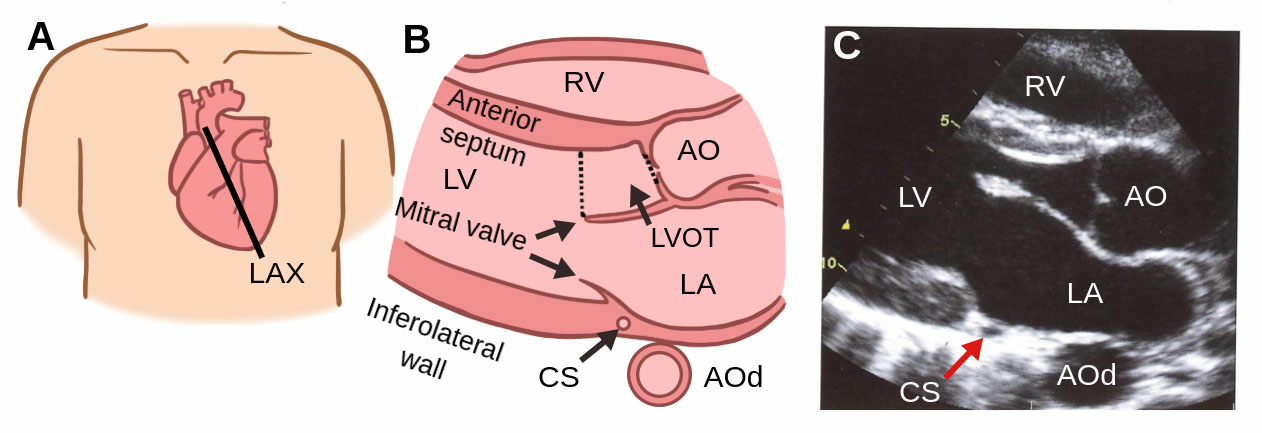

What is the parasternal LAX?

Parasternal long axis view, this is where the heart is sliced vertically.

Where on the body is the LAX view performed?

Between the 3rd-5th intercostal space, where the transducer is close to the sternum, specifically the left sternal border.

In parasternal LAX, is the transducer close to the sternum or far?

Close.

Where should the orientation marker be pointing towards to obtain a parasternal LAX?

Towards the patient’s right shoulder. Image the heart inside the body.

Where is the anterior wall of the RV in a parasternal LAX view?

At the top of the view.

Where is the RV chamber in an parasternal LAX view?

At the top, below the anterior wall of the RV.

Where is the interventricular septum in a parasternal LAX view?

The tissue below the RV and above of the LV.

Where is the aortic root in a parasternal LAX view?

On the mid right part of the screen; to the right of the aortic valve.

Where is the aortic valve in a parasternal LAX view?

To the left of the aortic root.

Where is the LV outflow tract in a parasternal LAX view?

To the left of the aortic valve.

Where is the LA in a parasternal LAX view?

36

Where is the mitral valve in a parasternal LAX view?

37

Where is the coronary sinus in a parasternal LAX view?

(hard to see in this picture)

Where is the descending aorta in this picture?

(not visible in this picture but it is circled where it would be)

Where is the LV posterior wall (LVPW or inferolateral wall)?

42